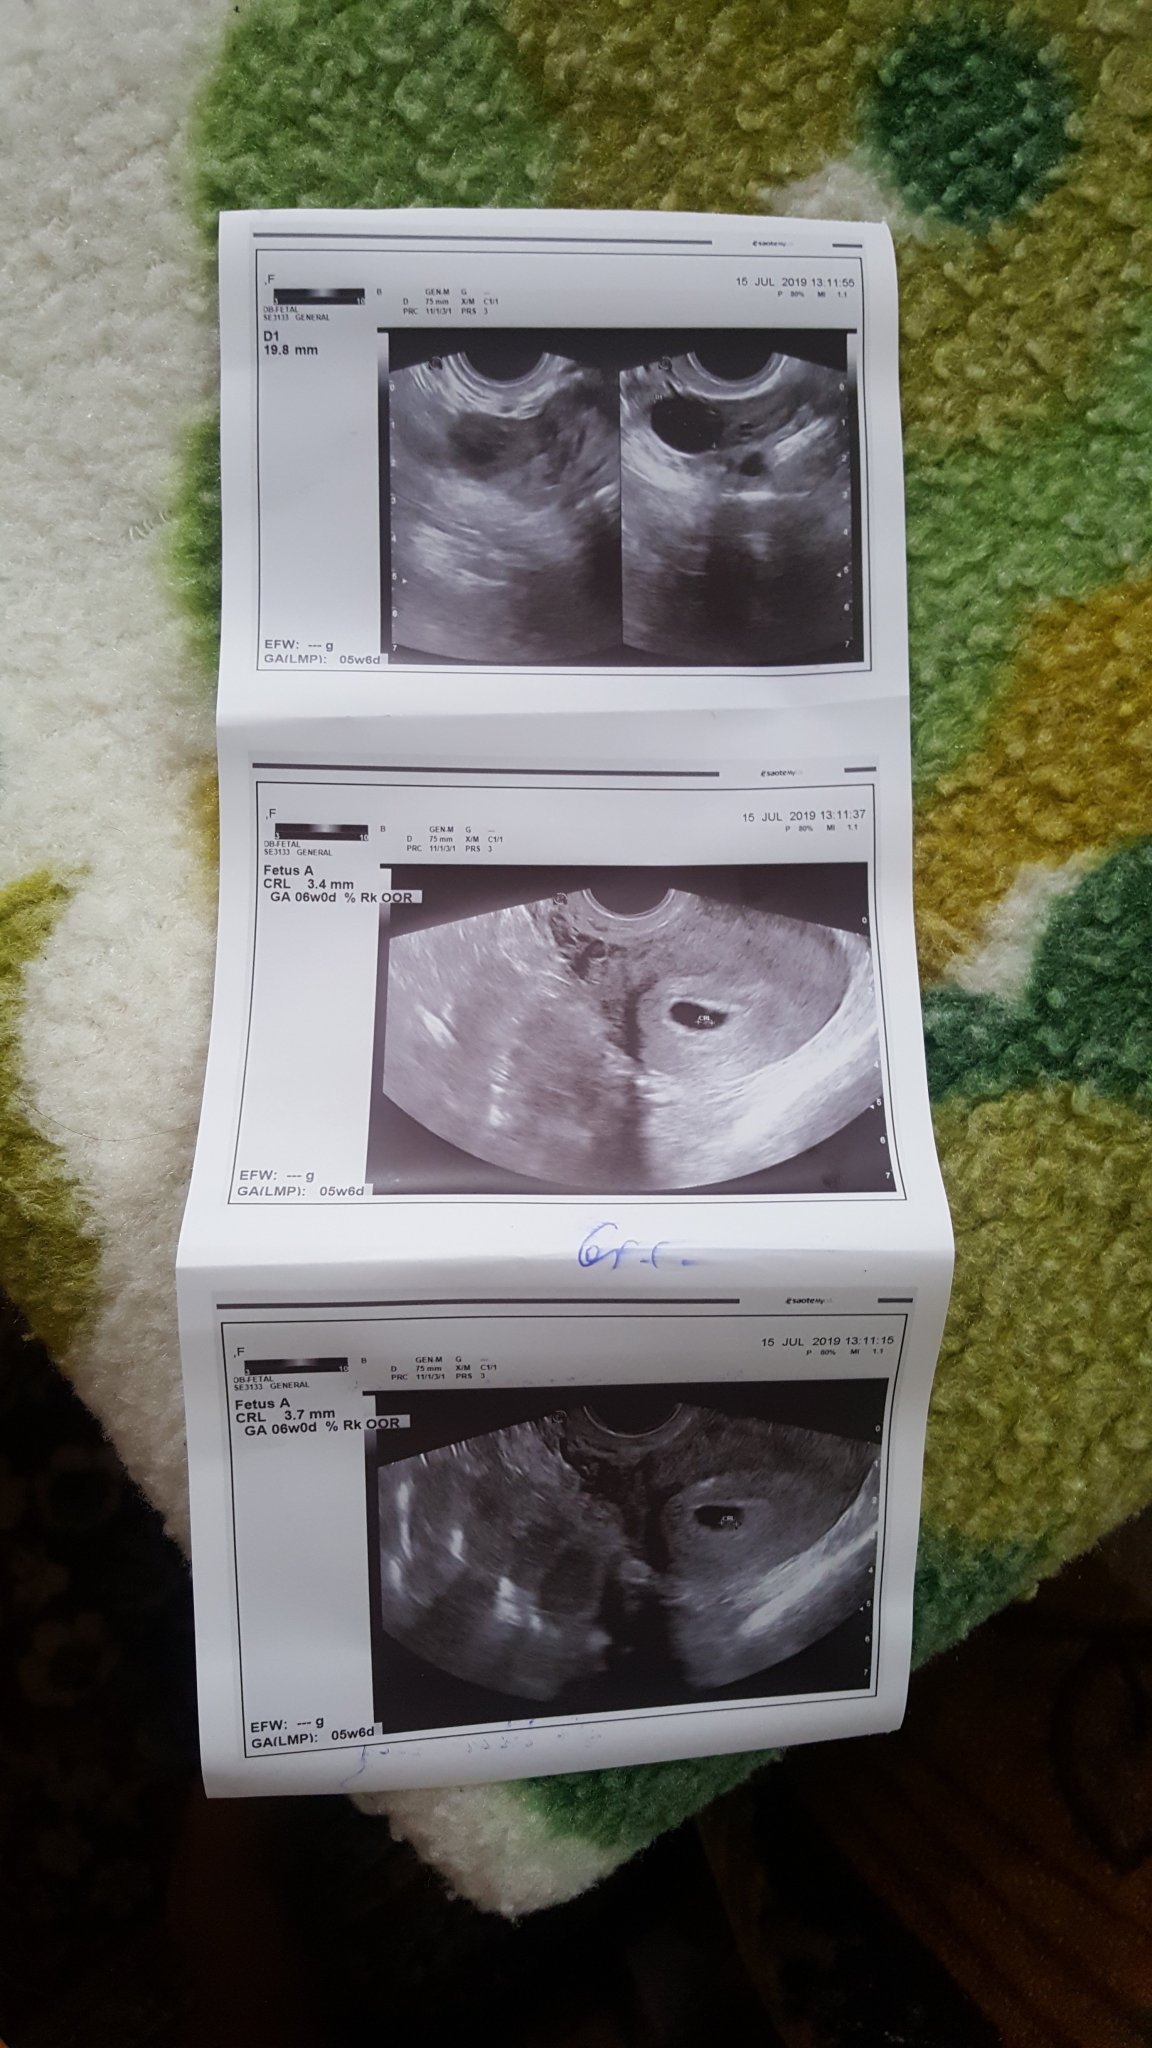

А ето и моето момиче да го видите.

Здравейте на всички.И аз току-що се връщам от преглед и се видя сърдечната дейност.В 5г.6дни съм.Много съм щастлива.На преглед съм на 1ви.Само се чудя дали да съм при тази док.или във Вита при д-р Чорбова..Едната(тази,при която бях днес във ВМА)е колежка на леля ми,а другата не я знам.При колежката ме спира това,че ВМА ми е по-далече от Вита(живея в Драгалевци),освен това там е ужас за паркиране,асансьорите са бавни и...няма друго.Сега в четвъртък съм при д-рката от Вита и тогава ще реша при коя да съм...